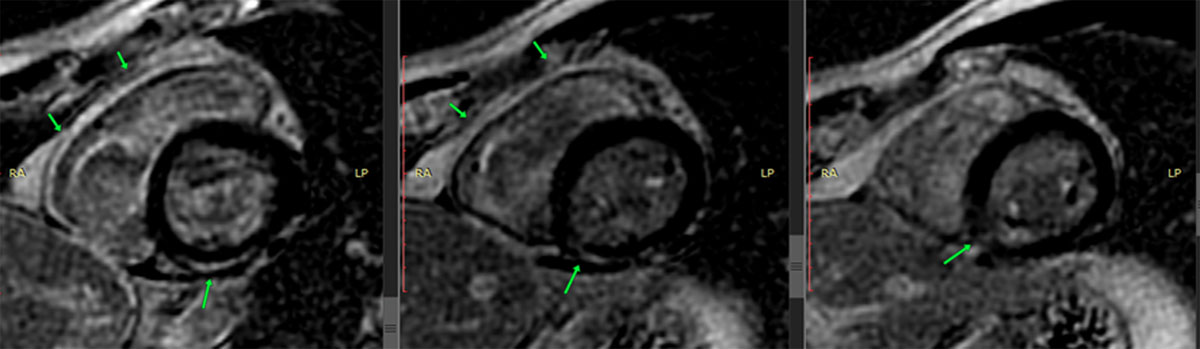

Figure 5

Cardiac MRI with late gadolinium enhancement in the inferoseptal, inferior, and inferomedial segments.